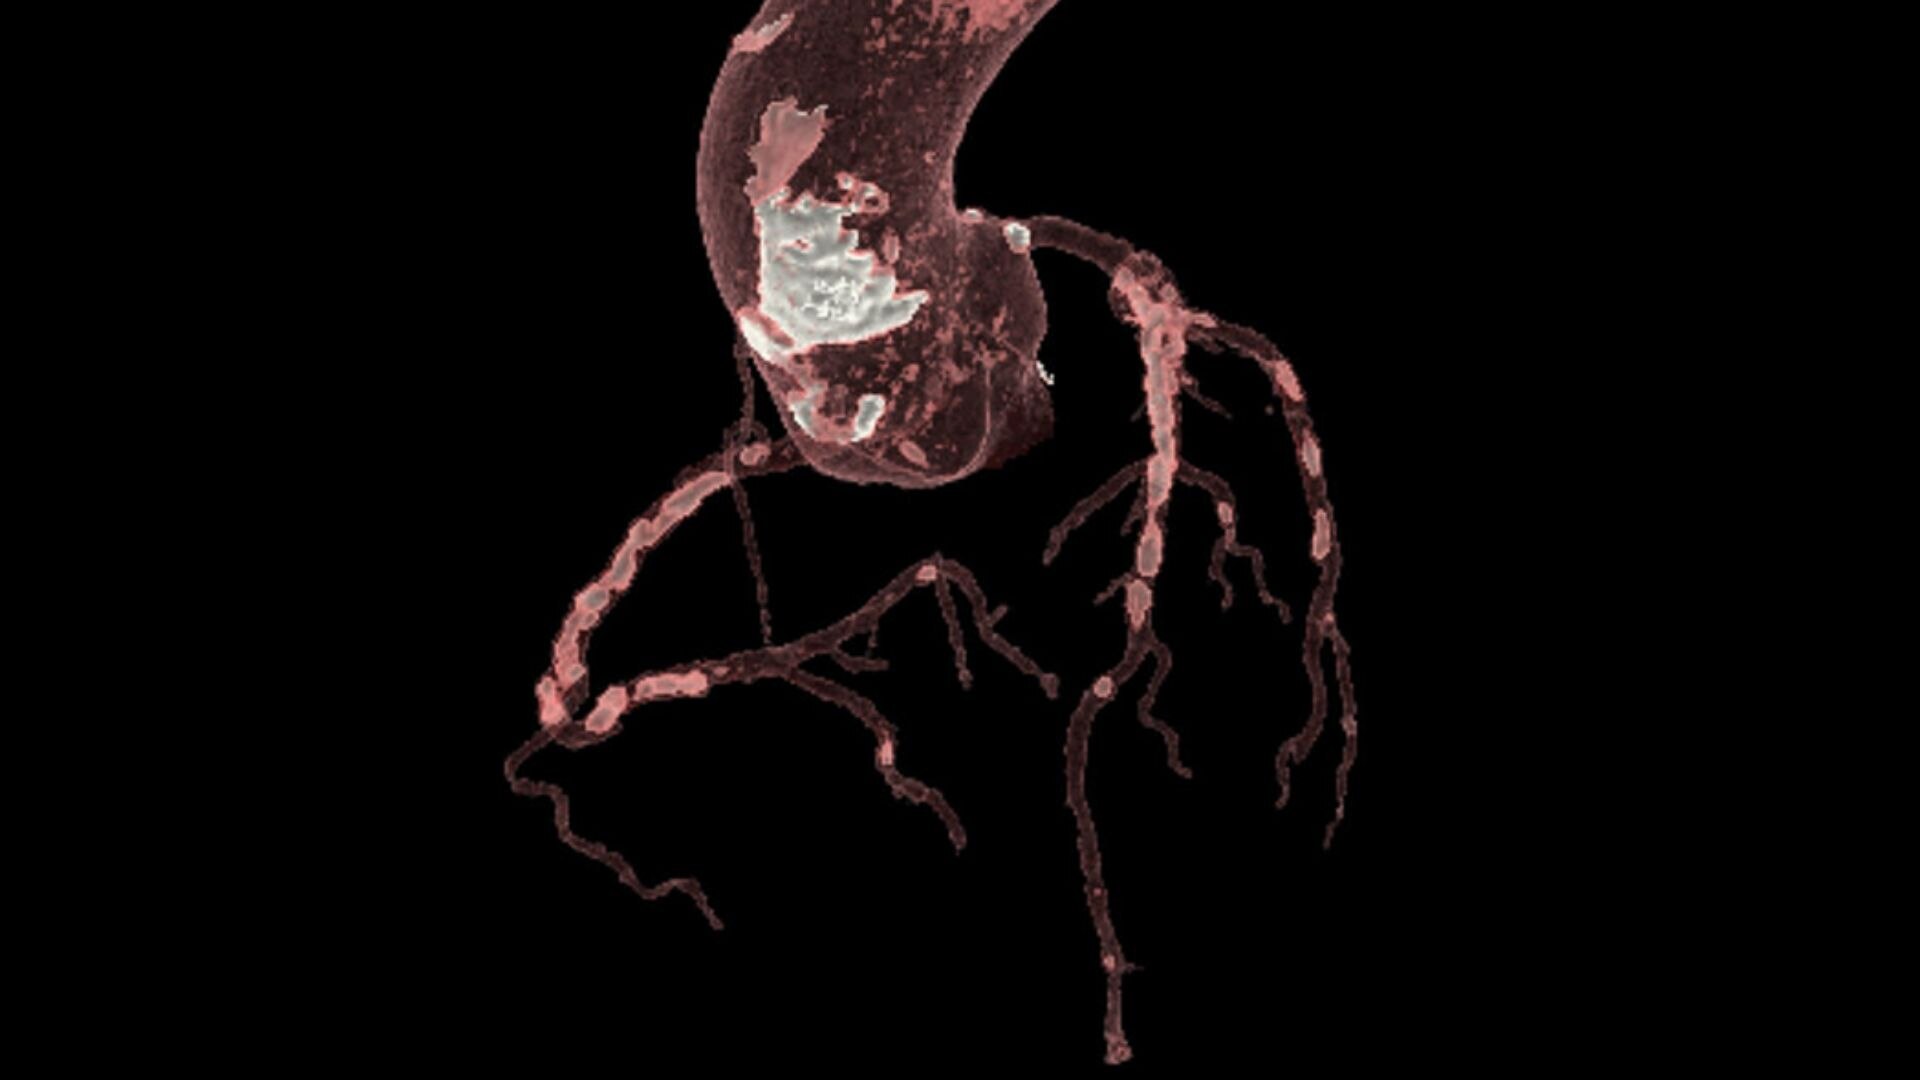

Discover the advanced capabilities of the SIGNA™ Architect, GE HealthCare's 3T magnet MRI system. Featuring a 128-channel Total Digital Imaging (TDI) receive chain and exceptional 44mT/m @ 200T/m/s gradient performance, this system sets a high standard for precision. Streamline your workflow effortlessly with products like AIR™ Recon DL, AIR™ Coils, and Sonic DL™, designed to enhance your diagnostic efficiency.

Elevated patient experience